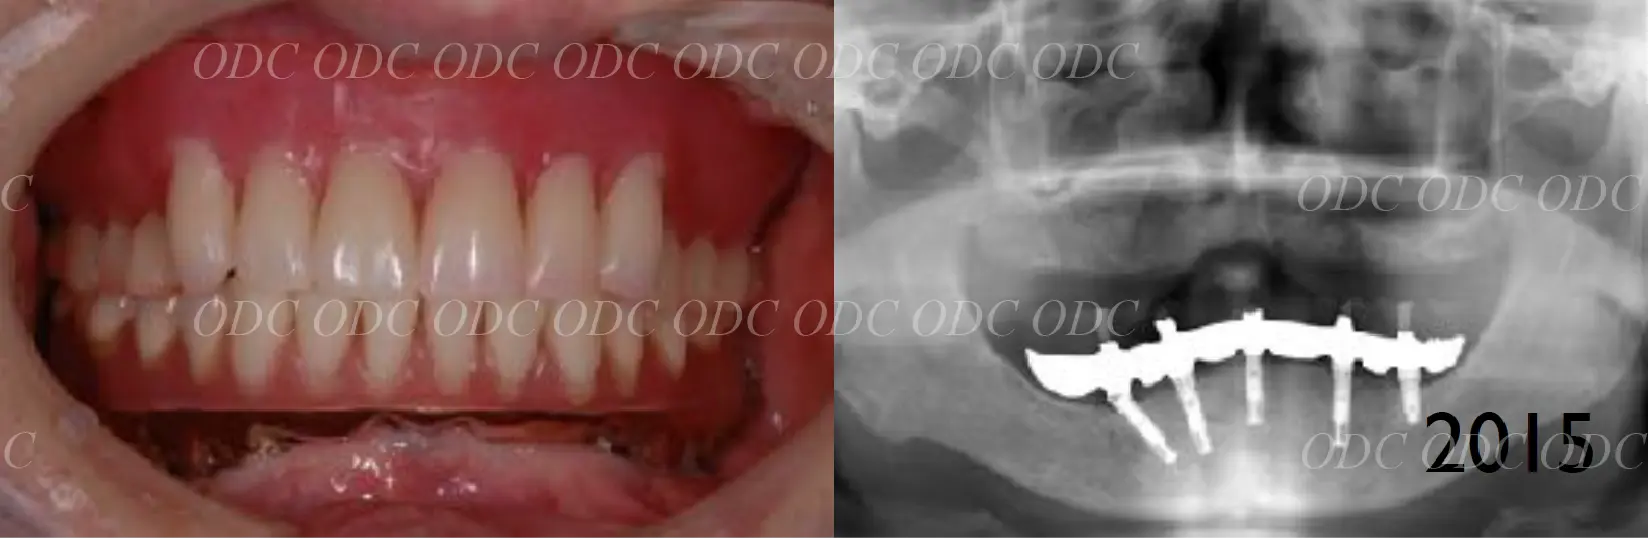

インプラントオーバーデンチャー症例

2011年

インプラントオーバーデンチャーとは、インプラントで入れ歯を支える方法です。

清掃がしやすいなどのメリットがあります。

また、多くの入れ歯の方が気持ち悪いと言われる上顎の内側の部分を大きく開けることができます。

上顎はCADCAMで作製されたバーを使用し、ロケーターとクリップを併用しています。

下顎は、ロケーターと呼ばれるアタッチメントで入れ歯が安定するようにしています。

インプラントオーバーデンチャーは、できれば3本以上のインプラントを使用すると安定しやすくなります。

2024年

治療終了後約13年経過しますが、上の入れ歯の前歯部分が破折してきて修理しています。

インプラントオーバーデンチャーは、掃除がしやすいなどのメリットはありますが、固定式のタイプと比較して摩耗しやすく、割れやすい等のトラブルは多くなることを覚えておいた方がいいでしょう。